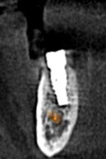

(7.) Postoperative CBCT images confirming implant placement according to the digital plan.

Figure 7

(8.) Postoperative CBCT images confirming implant placement according to the digital plan.

Figure 8